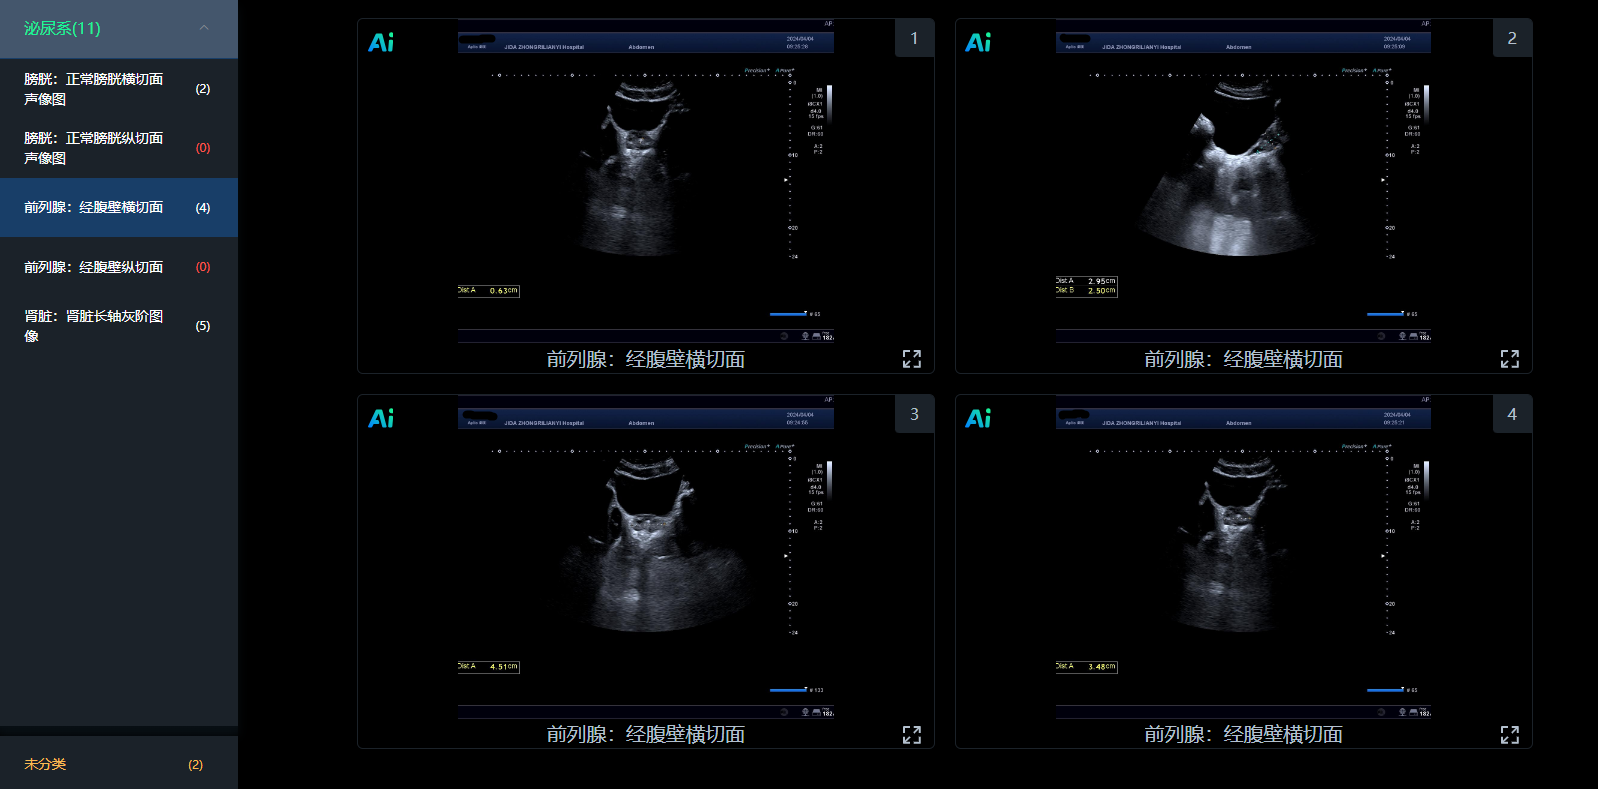

ai图像智控:检查即质控

基于cnn transformer混合架构的创新ai影像算法平台,事中风险管控,事后数据分析,通过ai赋能,实现了图像质控的智能化升级,高效精准。